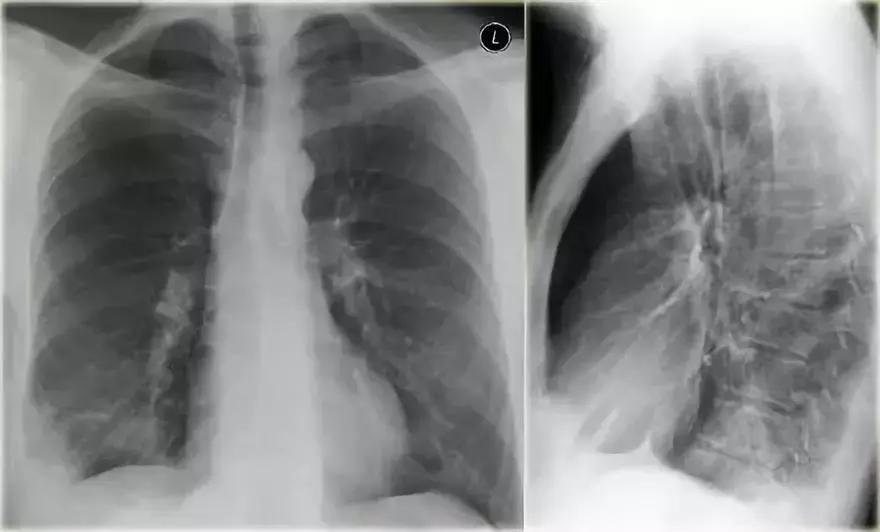

(1)影像一

图3 典型大叶实变

影像学表现:

➢ 左下肺边界模糊的密度增加的阴影

➢ 依然可见心脏轮廓,阴影出现在下叶

➢ 空气-支气管征

➢大叶性实变始于外周,由肺泡孔氏孔扩散

➢边界实变,由于一些肺泡参与实变,一些肺泡没有涉及,导致边缘模糊➢当病变发展到叶间裂,形成尖锐的轮廓,实变不能越过叶间裂

➢支气管周围肺泡更加密集,所以支气管相对更加明显可见,形成空气-支气管征(箭头所示)

➢肺实变时,肺体积应该没有或仅有轻微缩减。与肺不张有明显的不同

➢一般实变不会引起肺体积增大,但可见于克雷伯杆菌,时见于肺炎链球菌、TB和肺癌伴阻塞性肺炎